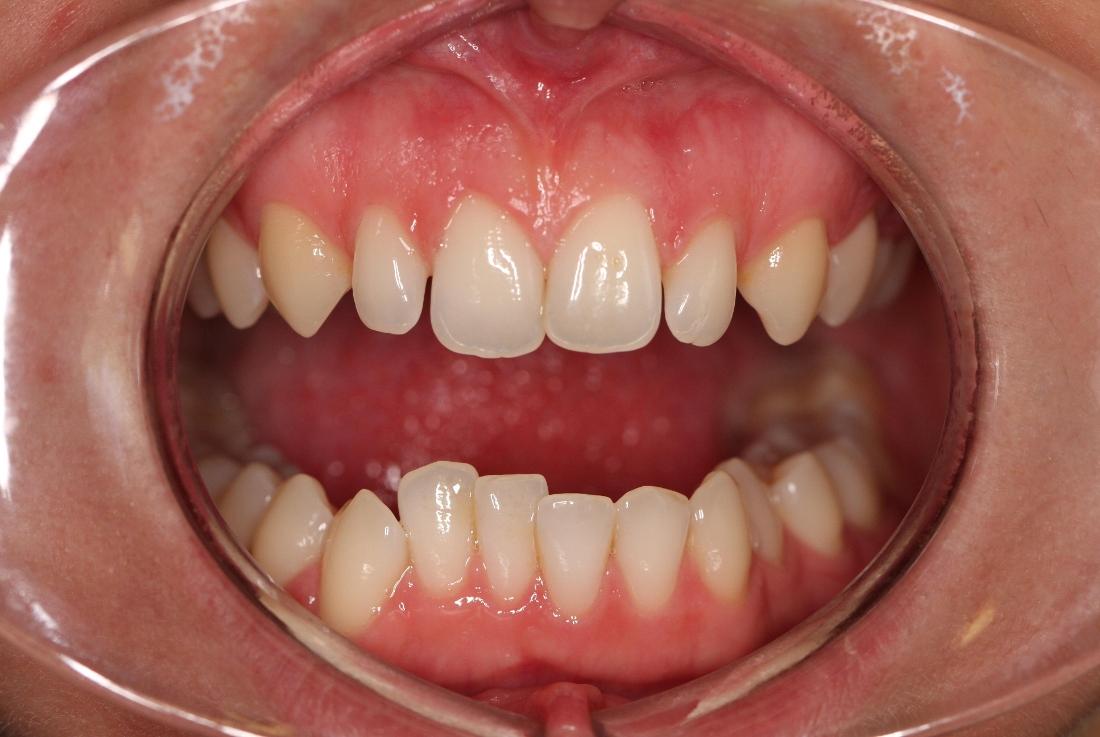

This young woman was self conscious about the crowding in her upper and lower teeth. After months of invisalign treatment, she is very satisfied with the result.